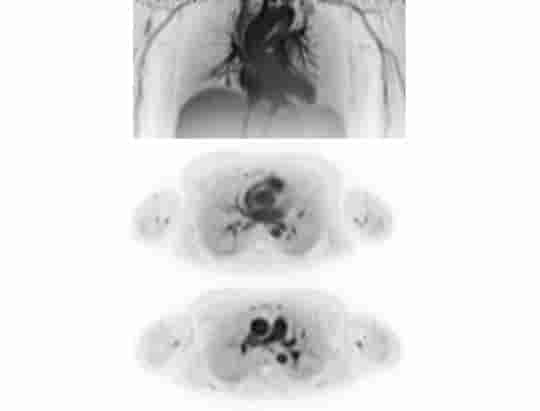

Przejrzystość obrazów uzyskiwanych z użyciem uMI Panorama wykracza poza pojedynczy parametr. System zapewnia wynoszącą 2,9 mm rozdzielczość PET wg NEMA oraz rozdzielczość czasową poniżej 200 ps, a 160-warstwowy tomograf komputerowy wykonuje pełny obrót w czasie 0,25 s z rozdzielczością przestrzenną 0,22 mm, gwarantując wysoką dokładność ilościową i wykrywalność małych zmian.

Urządzenie uMI Panorama wykorzystuje AI na każdym etapie badania – inteligentnie wykrywa pacjenta na stole w celu dokładnego pozycjonowania, upraszcza przepływ pracy dzięki automatycznemu ustawieniu parametrów skanowania i generuje obrazy o niezwykle wysokiej rozdzielczości przy użyciu zaawansowanego, również obejmującego sztuczną inteligencję mechanizmu iteracyjnej rekonstrukcji wytrenowanego na danych całego ciała pozyskanych dzięki systemowi PET uEXPLORER®.